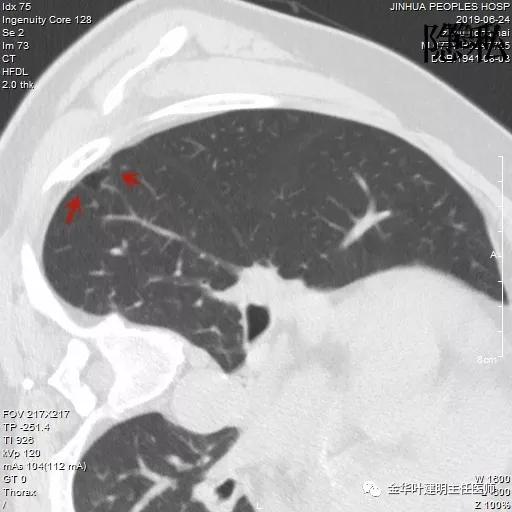

以上是2016年5月的片子,此处有非常小而淡的空腔性病灶,边缘略显磨玻璃,但仍说不上肯定的恶性。